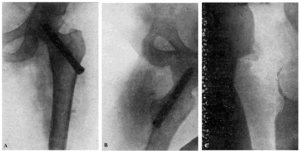

Teniendo en cuenta el mal estado general de la enferma se procede a la tracción continua, con ocho kilos de peso, mediante el procedimiento de Kirschner. A los ocho días ha mejorado extraordinariamente el estado general de la enferma, procediendo entonces a la osteosíntesis. Hay que advertir que la radiografía anteroposterior ha sido practicada antes de la completa penetración del clavo (fig. 2., A y B).

Figura 2. A: obs. núm. 8. Radiografía practicada antes de la completa penetración del clavo. Este está colocado en una posición demasiado craneal. B: Obs. núm. 8. El clavo fue colocado siguiendo la dirección del Kirschner superior. C: obs. núm. 8. El clavo se ha salido de la cabeza por su parte superior y su punta está situada a nivel de la parte superior de la caja cotiloide.

La radiografía (fig. 2., C) demuestra que el trocáncer ha ido ascendiendo, cortando el clavo el hemisferio superior de la cabeza hasta que, por haber chocado con la ceja cotiloidea, la ascensión del trocánter se ha detenido; pero entonces la pelvis ha basculado, ascendiendo la cresta ilíaca de este lado.

Actualmente nuestra mayor experiencia nos permite afirmar que el clavo, en este caso, había sido colocado demasiado cranealmente, y que, con toda probabilidad, una mejor exploración del estado general de la enferma nos hubiera indicado la inoperancia de la intervención.

Fracaso número 2(observación número 2). F. S., setenta años4. Ingresa en el servicio con una fractura mediana del cuello femoral izquierdo. Osteosíntesis extraarticular (fig. 3. A y B). La impactación no ha resultado perfecta.

Figura 3. A: obs. núm. 2. El clavo no penetra suficientemente y la impactación, salvo en la parte superior de la línea de fractura, es muy defectuosa. B: obs. núm. 2. La posición del clavo es buena. C: obs. núm. 2. El clavo tiende a ser expulsado hacia fuera y apenas penetra en la cabeza femoral.

A los veinte días de la intervención pasa el enfermo a su domicilio, recomendándole que continúe en la cama. Pasado un mes vemos nuevamente al enfermo, el cual nos manifiesta que anda con mucha más dificultad que en los primeros días de permanecer en su domicilio, que fue cuando, por no haber interpretado bien nuestras indicaciones, comenzó a emprender la marcha. La radiografía (fig. 3. C) demuestra que el clavo apenas penetra en la cabeza femoral. A los ocho días hacemos otra radiografía (fig. 4. A), observándose que el trocáncer ha ascendido, a pesar de continuar guardando cama el enfermo. Ingresa nuevamente en el servicio, donde, con anestesia raquídea, retiramos el clavo, reduciendo las fracturas y volviendo a colocar un clavo más largo en buena dirección (fig. 4. B). Una radiografía practicada siete años y medio más tarde demuestra la no consolidación de la fractura, trastornos tróficos en cuello y cabeza femoral y que el cabo ha penetrado en el fondo de la cavidad cotiloidea, en donde ha labrado una cavidad (fig. 4. C).

Figura 4. A: obs. núm. 2. El trocánter ha ascendido francamente con relación a la radiografía anterior. El clavo tiende a salir de la cabeza por su parte superior. B: obs. núm. 2. Se extrajo el clavo y se colocó otro. El nuevo clavo está colocado en buena dirección, pero la reducción no es perfecta. C: obs. núm. 2. El clavo ha penetrado en el fondo de la cavidad cotiloidea, en cuyo lugar ha labrado una cavidad. Trastornos tróficos en cuello ycabeza femoral. El cuello del fémur ha desaparecido casi completamente.

En este caso el fracaso se debe a que la impactación no fue perfecta, y sobre todo, a haber el enfermo iniciado la deambulación al mes de intervenido, a pesar de que nosotros le ordenamos que guardara cama.

Fracaso número 3(observación número 7). Carmen J., sesenta años. A los cincuenta y tres días de presentar una fractura transcervical del cuello del fémur intentamos el enclavijamiento, que no pudimos realizar por no funcionar los rayos X a causa de una avería eléctrica. No pudimos repetir la intervención hasta pasados veinticuatro días, resultándonos entonces imposible reducir correctamente la fractura (fig. 5., A y B). Enclavijamiento (fig. 5. C) técnicamente defectuoso. A los cuatro meses a causa de presentar una supuración en la herida ingresa nuevamente en el servicio. Una radiografía practicada la misma tarde demuestra la ascensión del clavo, el cual está a punto de perforar el borde superior de la cabeza. Un mes después se extrae dicho clavo. La radiografía parece demostrar una ausencia de consolidación. La enferma deambulaba relativamente bien con ayuda de un bastón.

Figura 5. A: obs. núm. 7. En esta proyección la reducción es, aparentemente, buena; sin embargo, la zona clara que existe a nivel de la línea de fractura, demuestra la ausencia de reducción. B: obs. núm. 7. La fractura no está reducida. C: observación núm. 7. El clavo ha sido colocado de-masiado cranealmente.

La causa fundamental del fracaso en esta observación reside en no haber reducido correctamente la fractura, cosa que hubiéramos conseguido con toda probabilidad gracias a una tracción continua mediante un Kirschner colocado en la metáfisis femoral inferior.